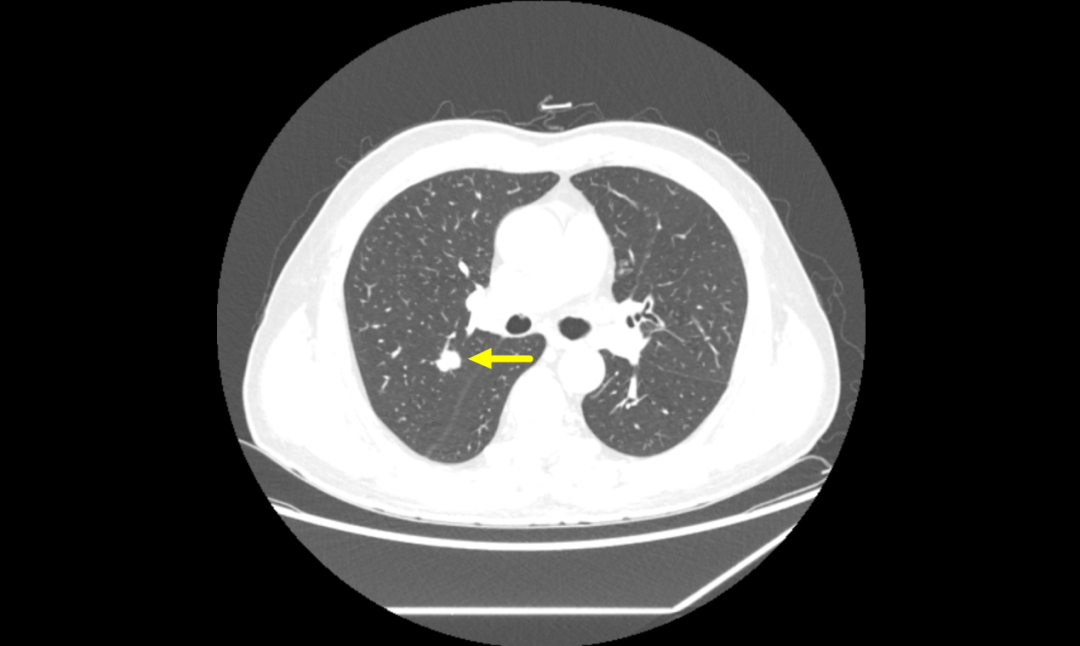

患者李伯,70岁,因“咳嗽、咳痰3月,发现肺部结节20天”入院。患者有慢性阻塞性肺病史,曾因膀胱结石行微创手术治疗,有30余年吸烟史。入院后查体发现双肺呼吸音低,胸部CT显示右肺上叶后段实性结节,有分叶、短毛刺,与血管相连,中度强化,考虑恶性可能性大。

▲胸部增强CT提示右肺结节,恶性可能性大